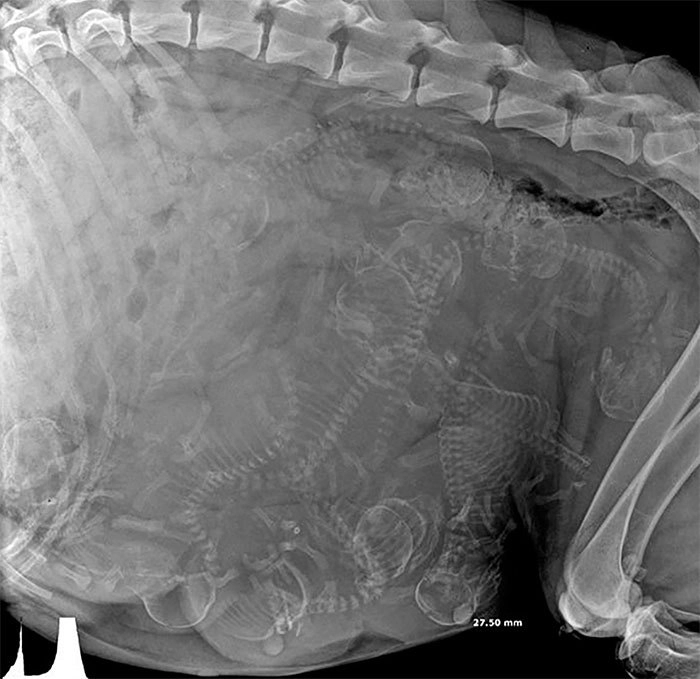

Рентген беременной кошки